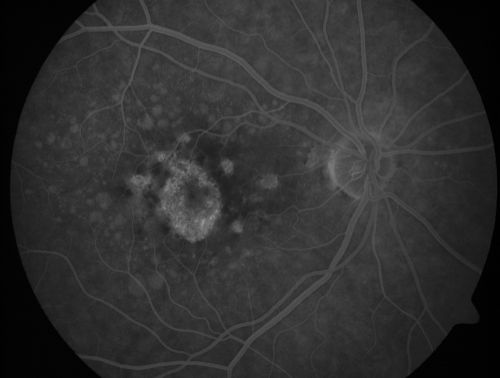

| Album name: | scohen125 / Geographic Atrophy - Previous Confluent Soft Macular Drusen |